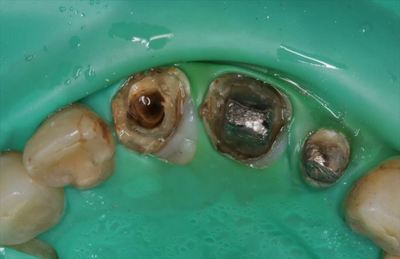

IMG_3986_R27.JPG

上顎の中切歯2本と左上側切歯の計3本のかぶせもの(レジン前装鋳造冠)を除去します。

上顎中切歯2本は連結冠でつながっています。